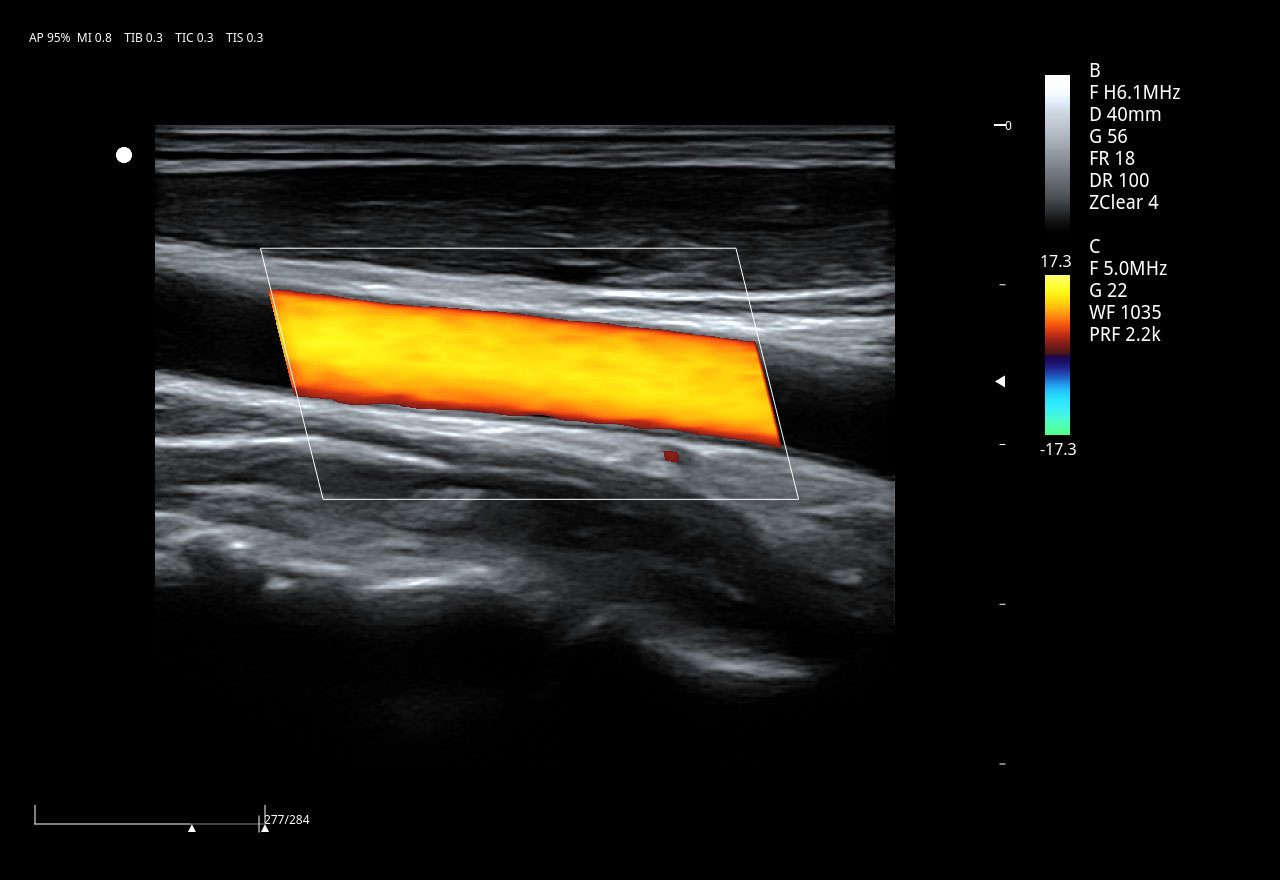

ViV20新一代全身应用型彩超,经济实用、简洁易用、皮实耐用,以其优异的图像性能、全面的功能配置,为一线临床提供超越预期的应用体验。

血管内中膜厚度自动测量 IMT

可以自动识别并自动测量血管内中膜的厚度,提供内中膜厚度测量报告,为心脑血管事件的预防提供独立的预测指标